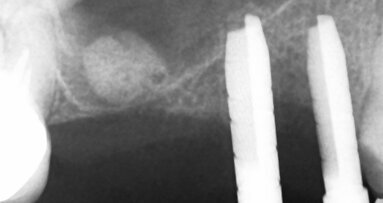

Náhrada PMMA je provizorium, které slouží k testování dosedů, anatomie a upřesňuje okluzní vztahy – štoly nejsou angulované. Na zubu číslo 23 je vidět otvor v incizní oblasti a je vizualizován budoucí otvor definitivní náhrady.

Návrh definitivní náhrady: angulace vyřešila problém narušení incizální hrany zubu 23